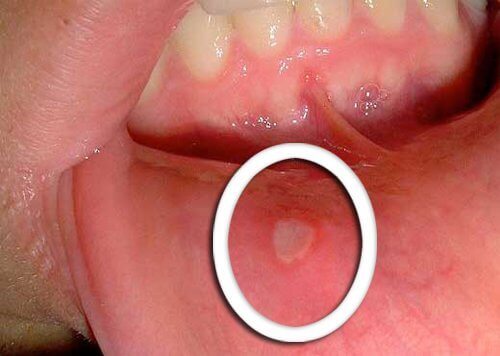

Фізичні зміни в ротовій порожнині

- Найбільш раннім серед симптомів ротоглоткового раку є маленькі ранки, які не загоюються.

- Характерно, що червоні або білі виразки з’являються на язиці, яснах або губах.

- Звертайте увагу на будь-які незвичайні зміни, які не проходять через кілька днів, і розкажіть про них лікарю.